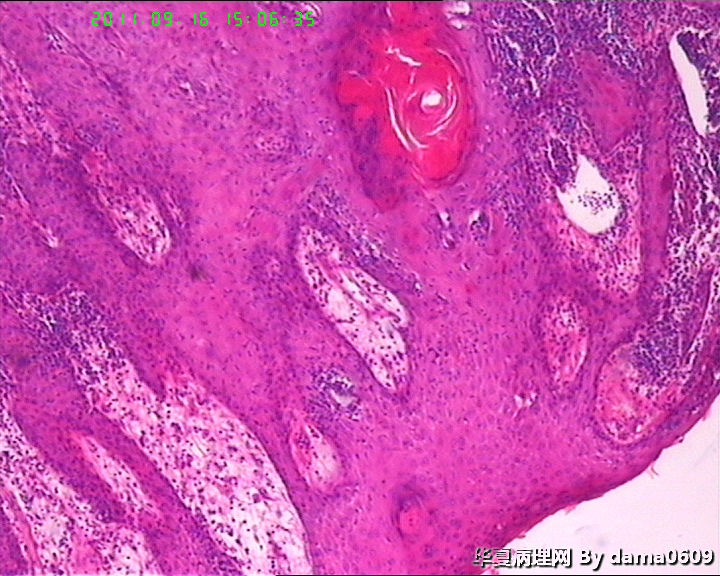

女,背部皮肤肿物,病史不详。送检梭皮组织一块,S:4.5x2.2cm,正中一圆形隆起,直径2.0cm,表面黄白色与周围界清,切面实性灰白色。

• 背部肿物,急请老师看看!!图1

图1